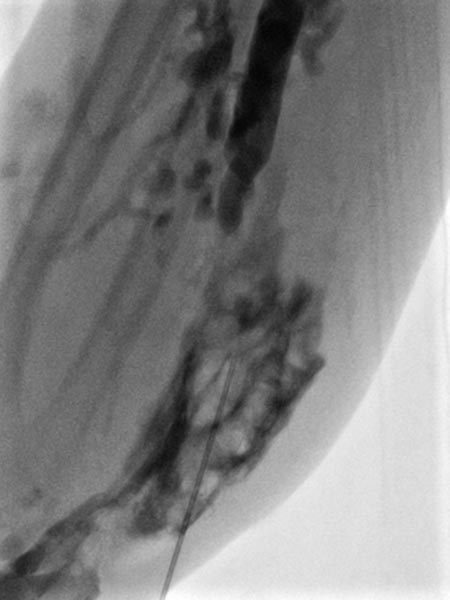

On account of the relatively small individual vessel diameters of the venous malformation, it is also difficult to puncture them directly. Varicography using a direct puncture technique shows multiple, rather elongated, partly reticular dysplastic small-lumen venous channels.

After the needle position is secured within the venous malformation and drainage via a major communicating vein is ruled out, polidocanol foam (3% Aethoxysklerol foamed 1 to 4 in air) is injected. This foam is not radiopaque but displaces the previously injected contrast material from the lesion.

Further proximally in the forearm, the entire venous malformation in the depth of the flexor muscles is also gradually injected with sclerosing foam.